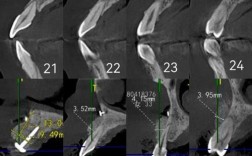

医生进行口腔检查,拍摄X光片、取牙模,评估牙齿和颌骨情况。